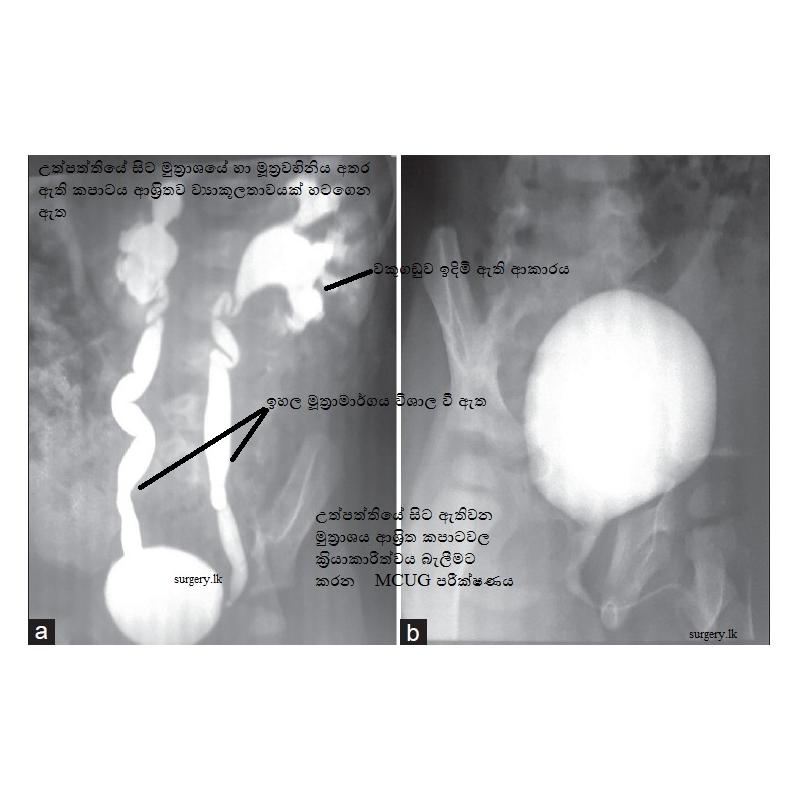

මීට අමතරව ස්කෑන් පරීක්ෂණද බොහෝවිට සිදුකරනු ලබන අතර එය බොහොමයක් උත්පත්තියේදී මූත‍්‍රාමාර්ගය ආශ‍්‍රිතව ඇති වූ ව්‍යාකූලතා හදුනා ගැනීම උපකාරී වේ.

අවශ්‍යතාව අනුව සමහර අවස්ථාවලදී විශේෂිත එක්ස්-රේ පරීක්ෂණ සිදුකරනු ලබයි.

නමුත් මෙම පරීක්ෂණය බොහෝවිට විෂබීජ තත්වයට ප‍්‍රථිකාර කිරීමෙන් පසු කරනු ලැබේ.

එයද උත්පත්තියේදී ඇති වූ ව්‍යාකූල තත්වයන් හදුනා ගැනීමට ඉවහල් වන පරීක්ෂණයකි.